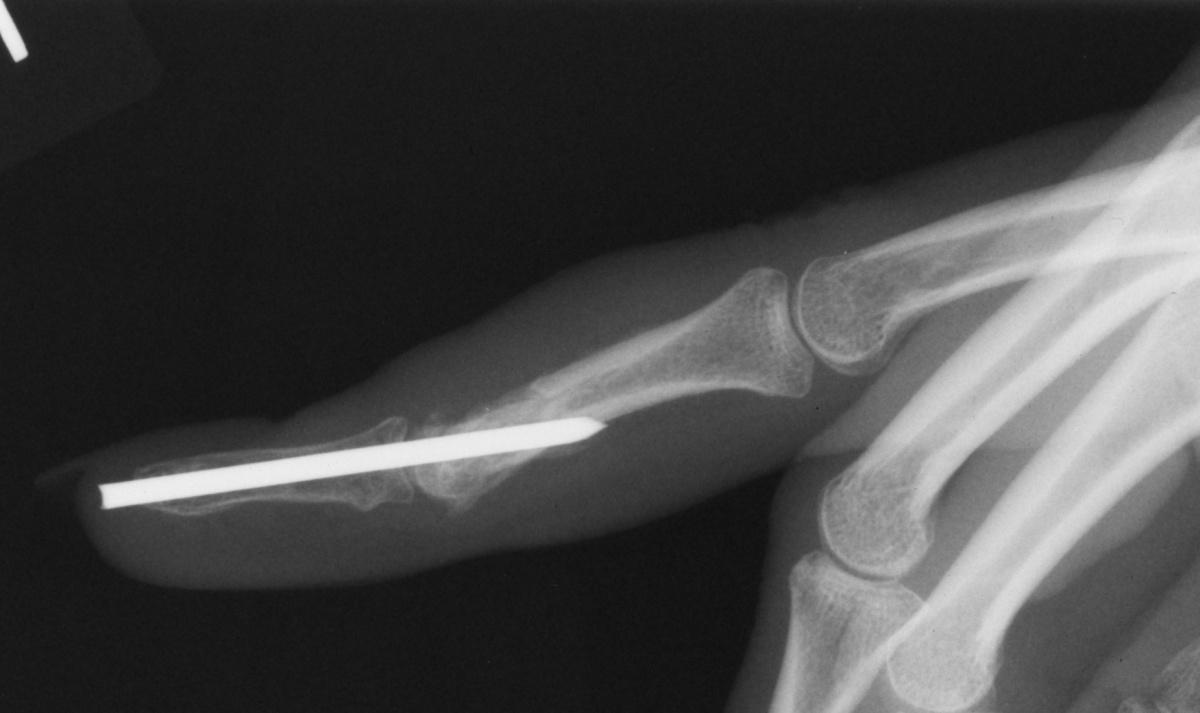

| Case 1. This 18 year old man

presented with a two year history of pain and swelling of the distal

aspect of his proximal phalanx. |

| Plain films showed

sclerosis within a radiolucent area and adjacent cortical/endosteal

sclerosis. |

| The tumor was removed with

a burr. |

| Despite extensive

resection, over three quarters of the cortical circumference remained,

and structural reinforcement was not necessary. |